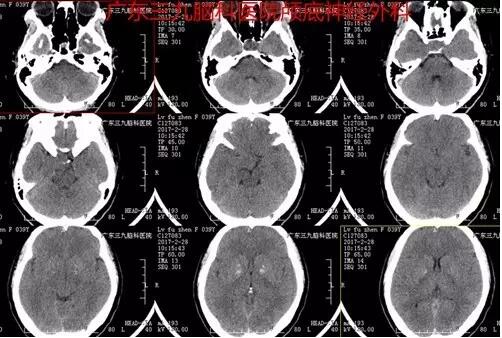

图1:术前CT提示额部类圆形等密度占位性病变